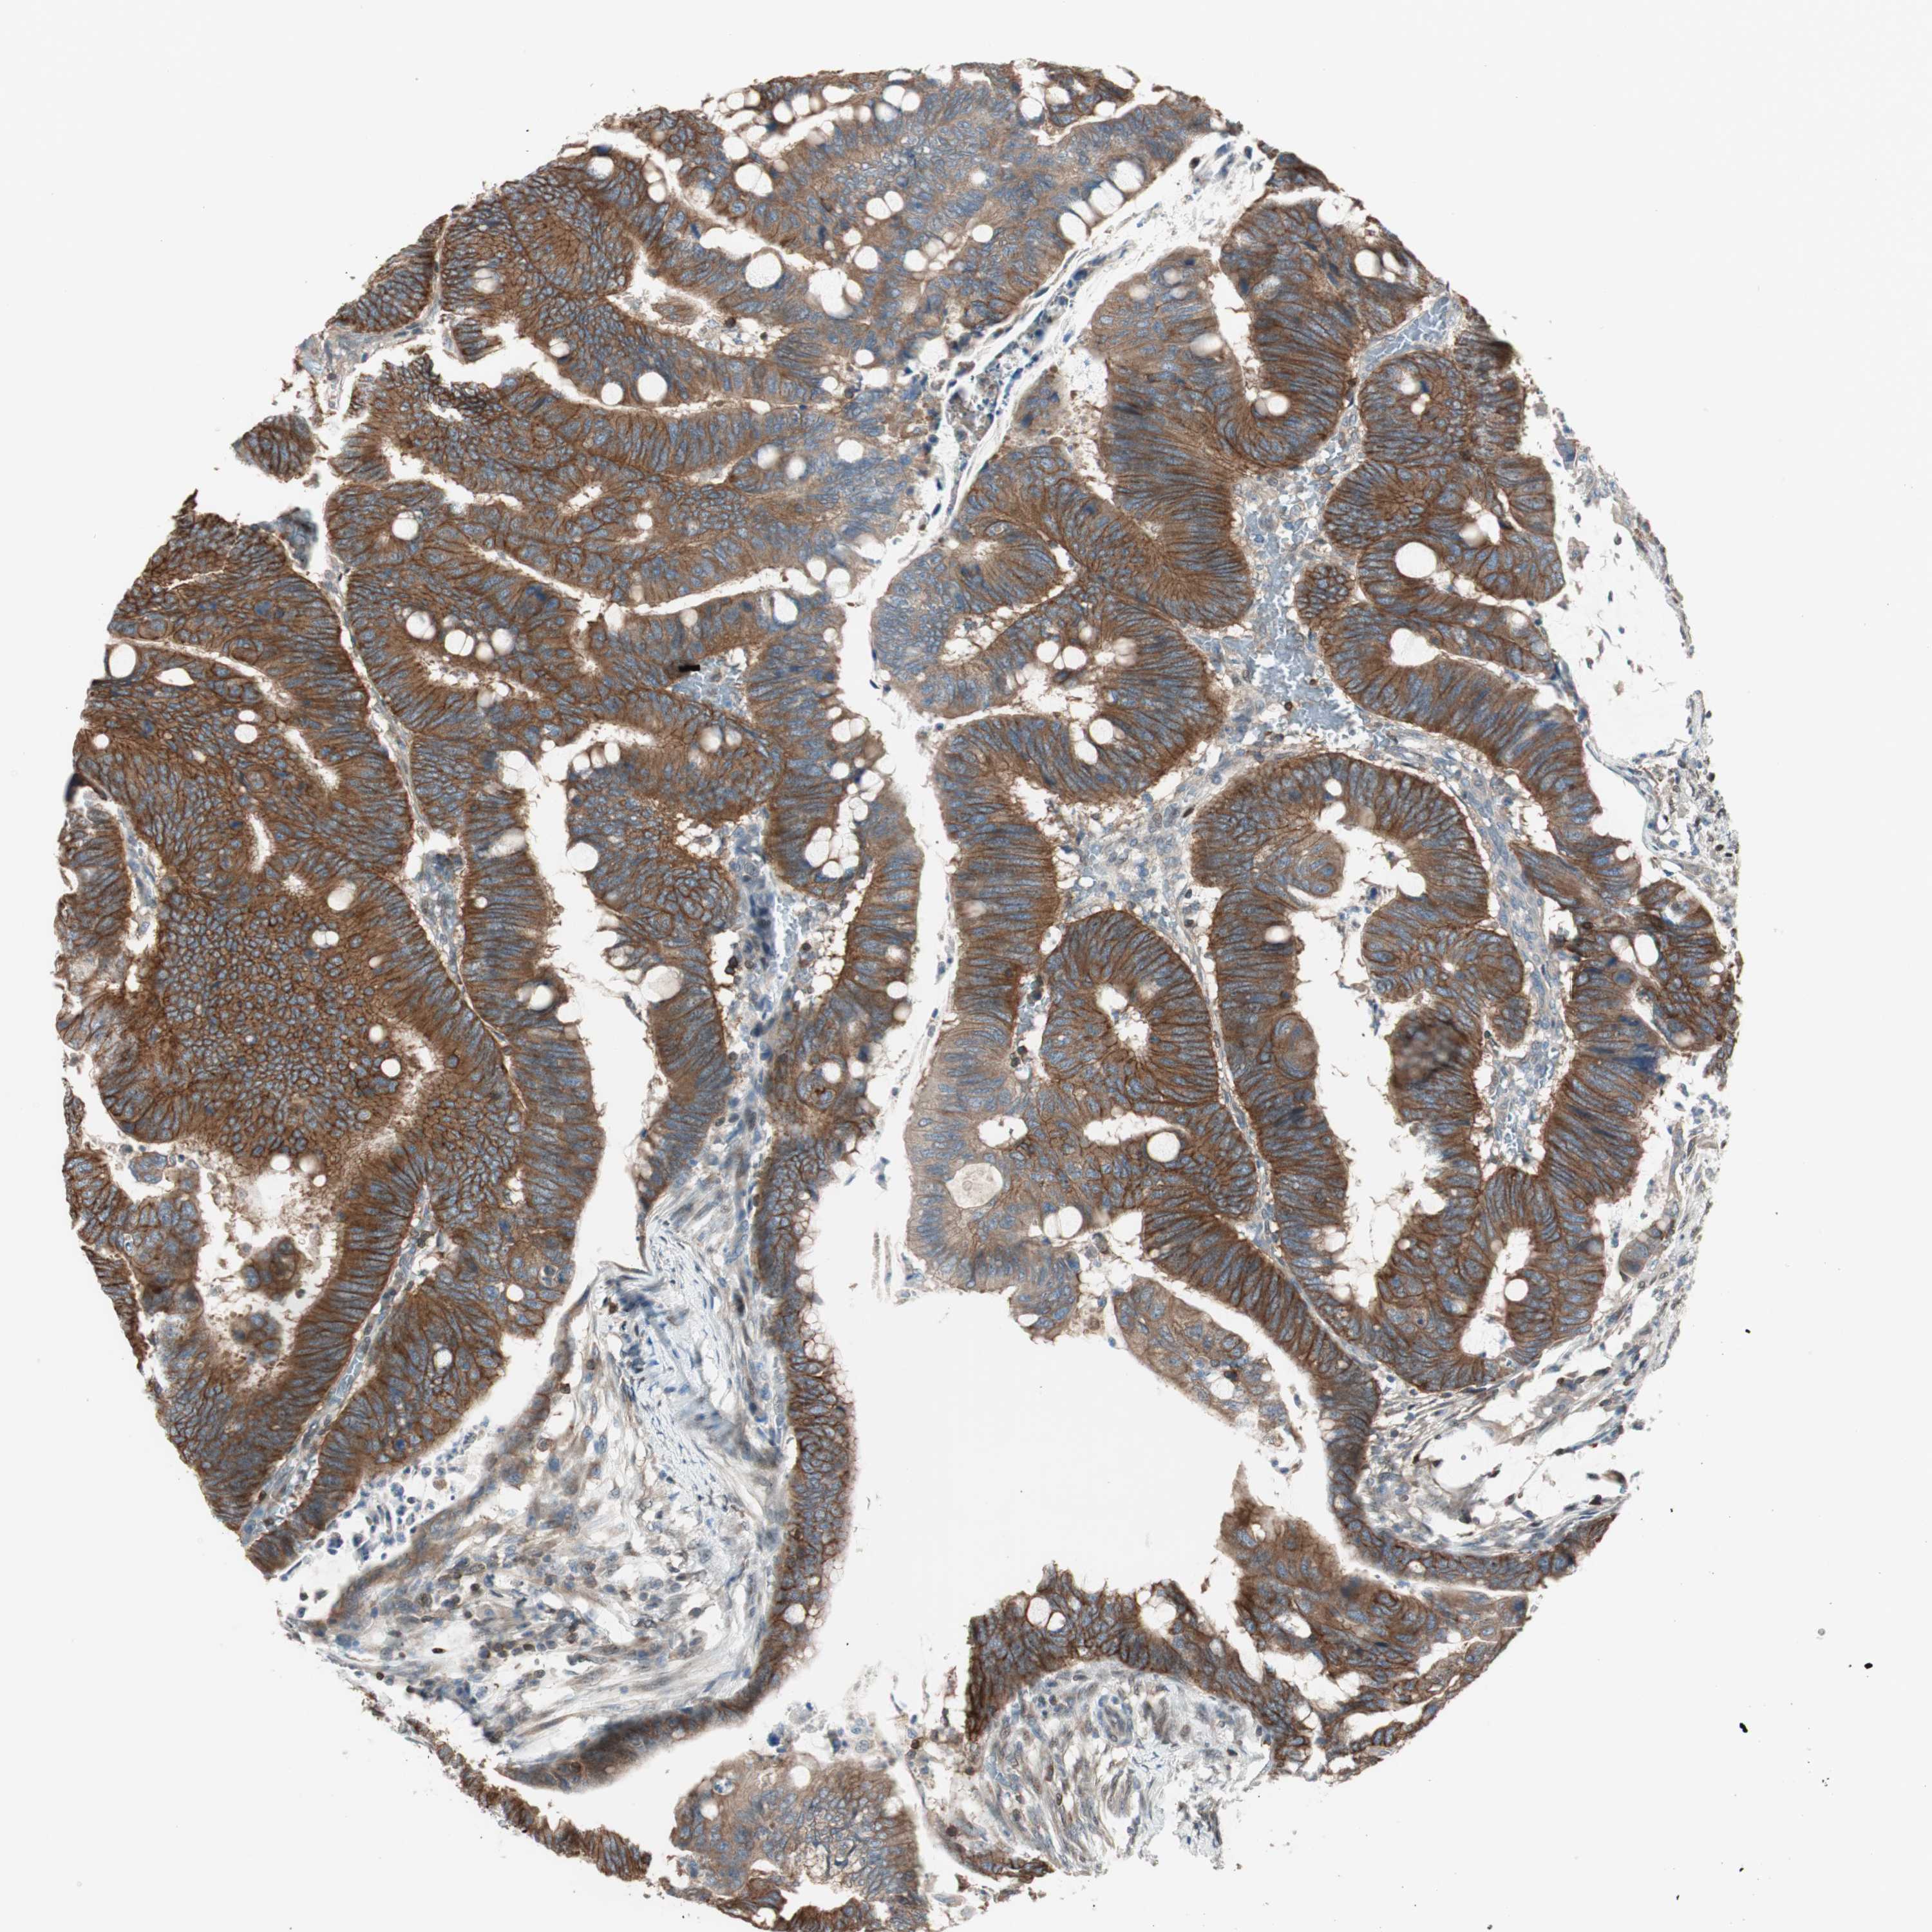

CANCER COLORECTAL CANCER Show tissue menu

Colorectal cancer

Human cancer

Colon adenocarcinoma